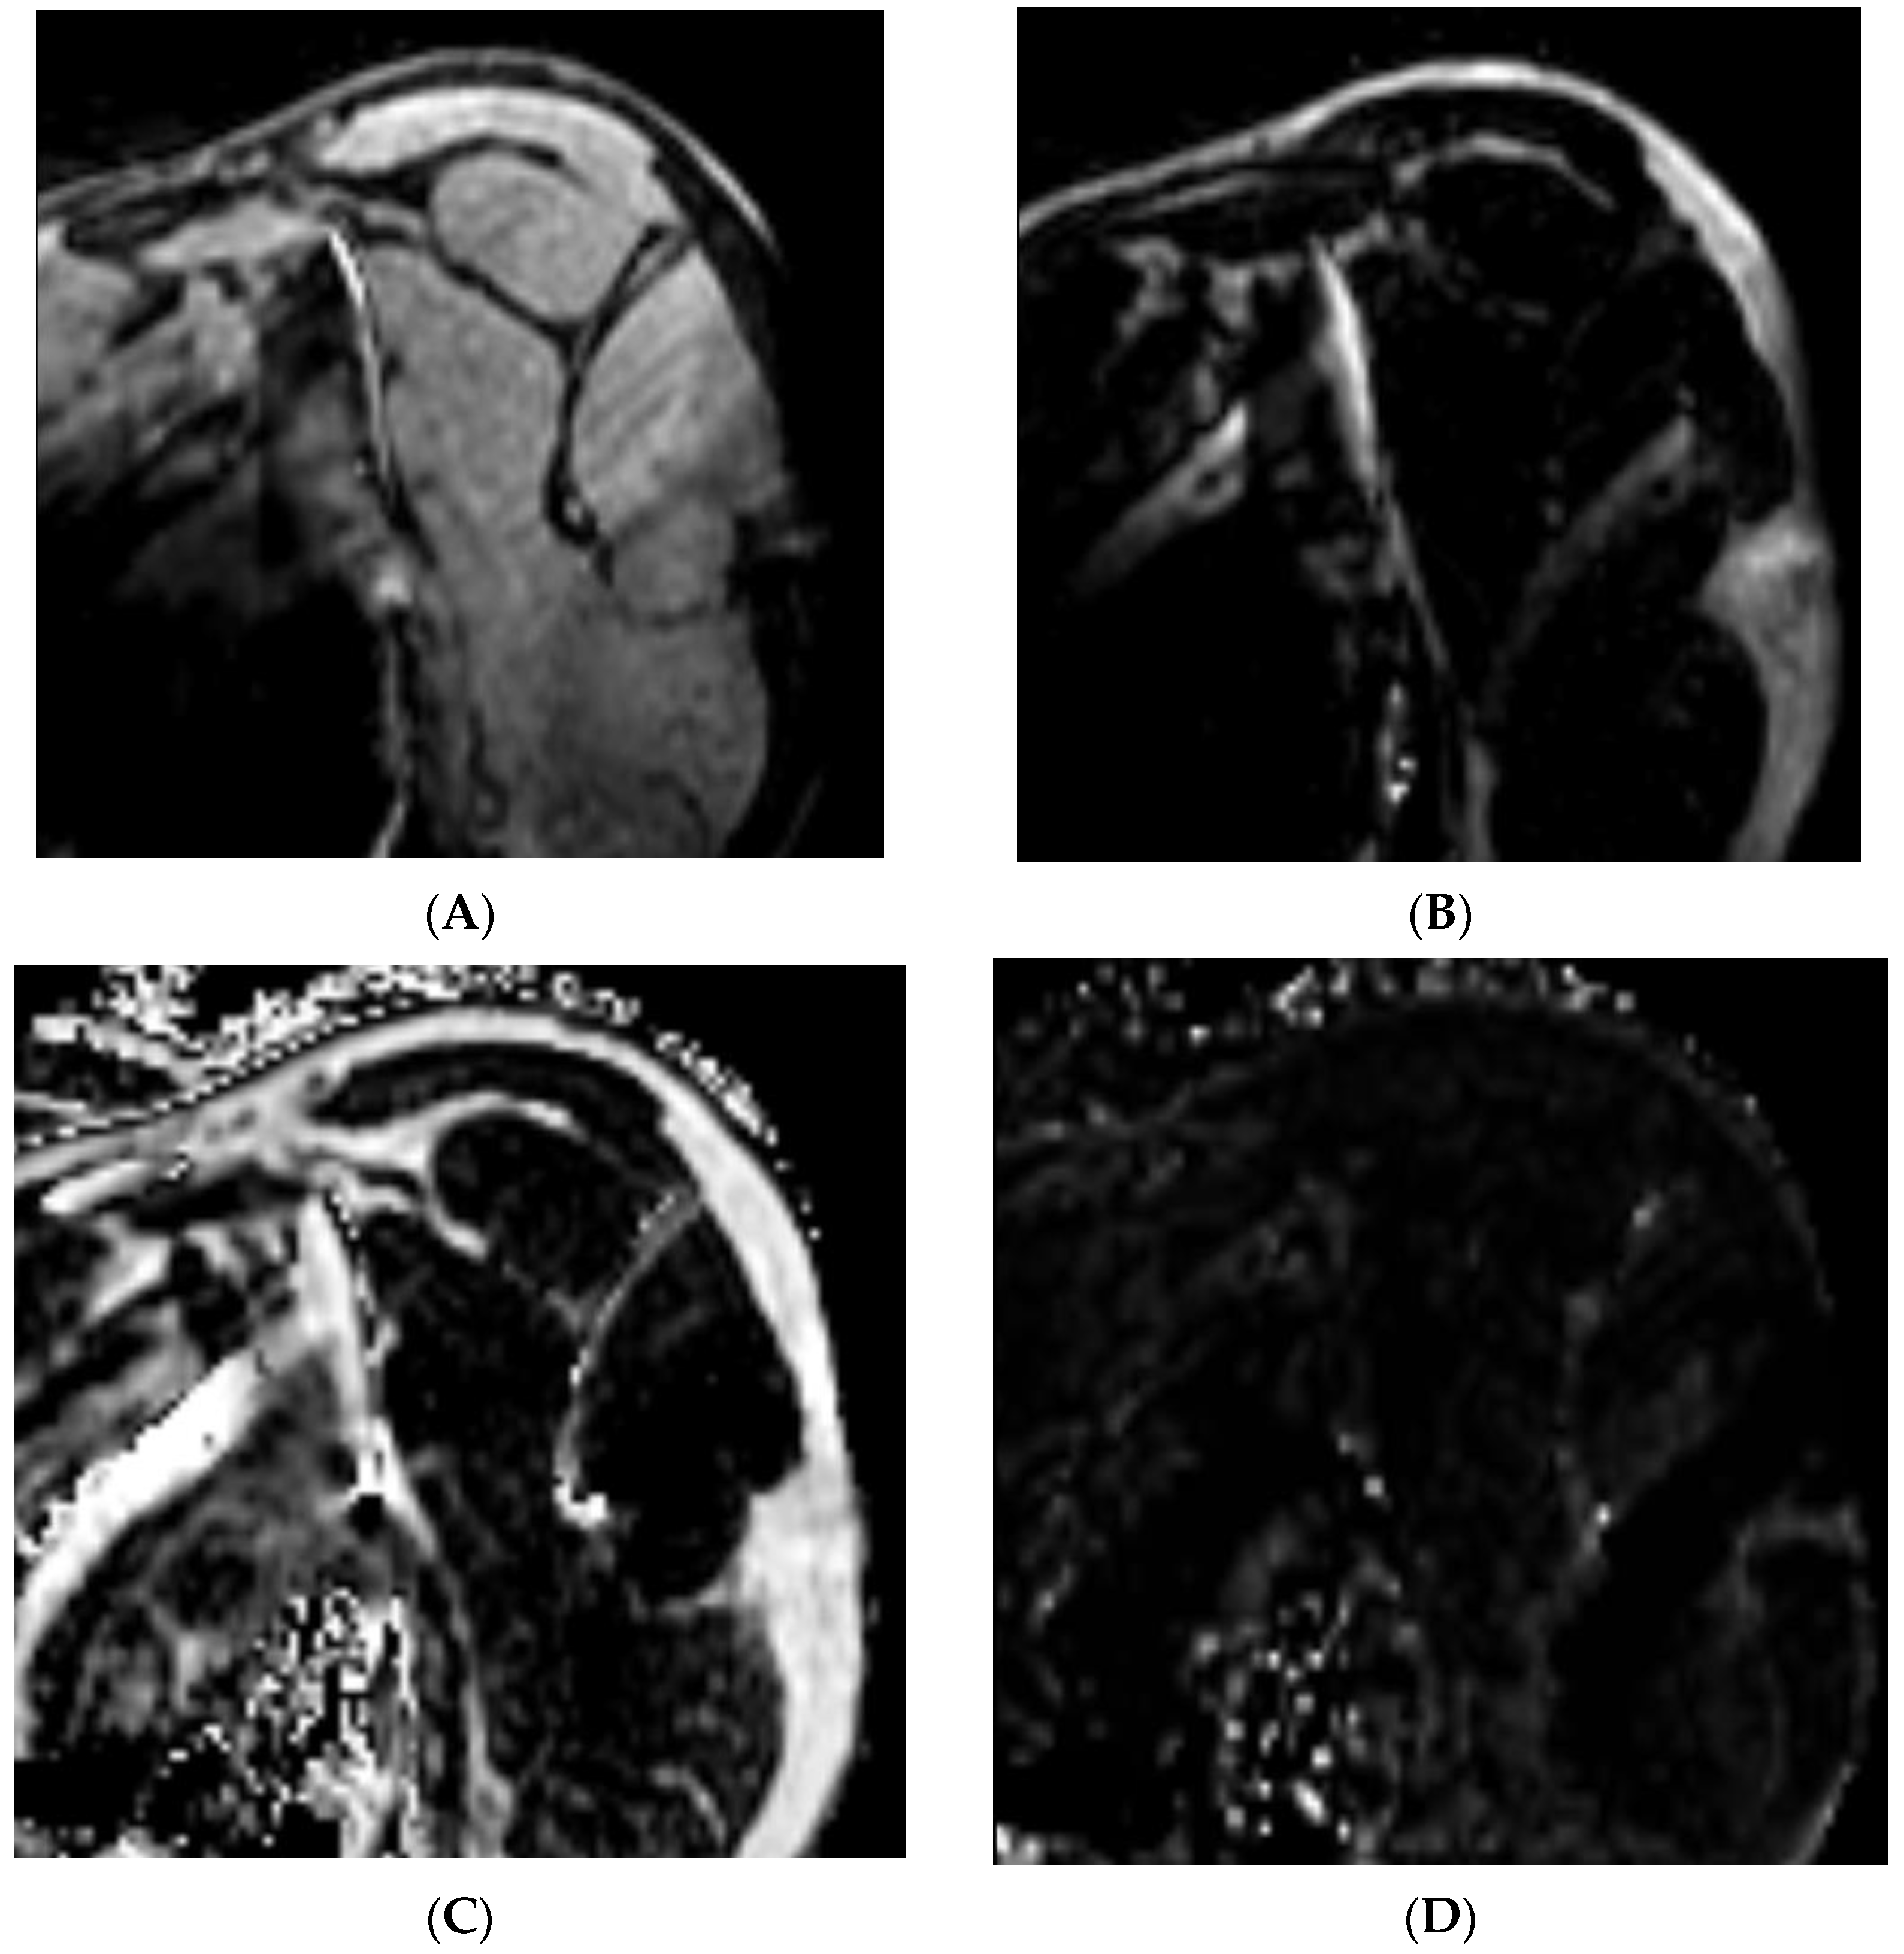

- Hahn, S.; Lee, Y.H.; Lee, H.S.; Song, H.-T.; Suh, J.-S. The Utility of Modified Dixon Turbo Spin Echo Shoulder Magnetic Resonance Arthrography in Assessing Rotator Cuff Disorder and Evaluating the Rotator Cuff Muscles. Acad. Radiol. 2021, 28, 233–242. [Google Scholar] [CrossRef] [PubMed]

- Lee, Y.H.; Kim, S.; Lim, D.; Song, H.-T.; Suh, J.-S. MR Quantification of the Fatty Fraction from T2*-corrected Dixon Fat/Water Separation Volume-interpolated Breathhold Examination (VIBE) in the Assessment of Muscle Atrophy in Rotator Cuff Tears. Acad. Radiol. 2015, 22, 909–917. [Google Scholar] [CrossRef]